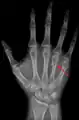

![]() Fourth metacarpal of the left hand (shown in red). Palmar view. | |

A fractured right hand fourth metacarpal (boxer's fracture).